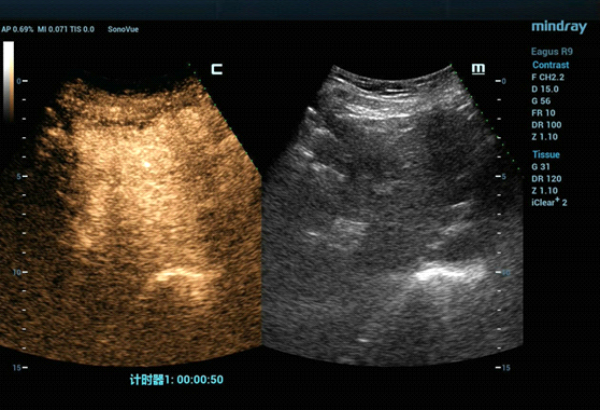

CT에서는 보였던 S4구역 재발성 간암은 일반 흑백초음파에서는 보이지 않았습니다. CEUS(Contrast-Enhanced Ultra Sound)영상에서는 동맥기에서는 과혈관 상태의 영상을 보였고 문맥가와 그 이후의 기에서는 사라지는 영상을 보여주었습니다.

형태 2. 동맥기에서 증강이 두드러짐. (측정 마커:S4 종괴)

형태 3. 간문맥 단계에서 보여주는 종괴의 등장성 증강